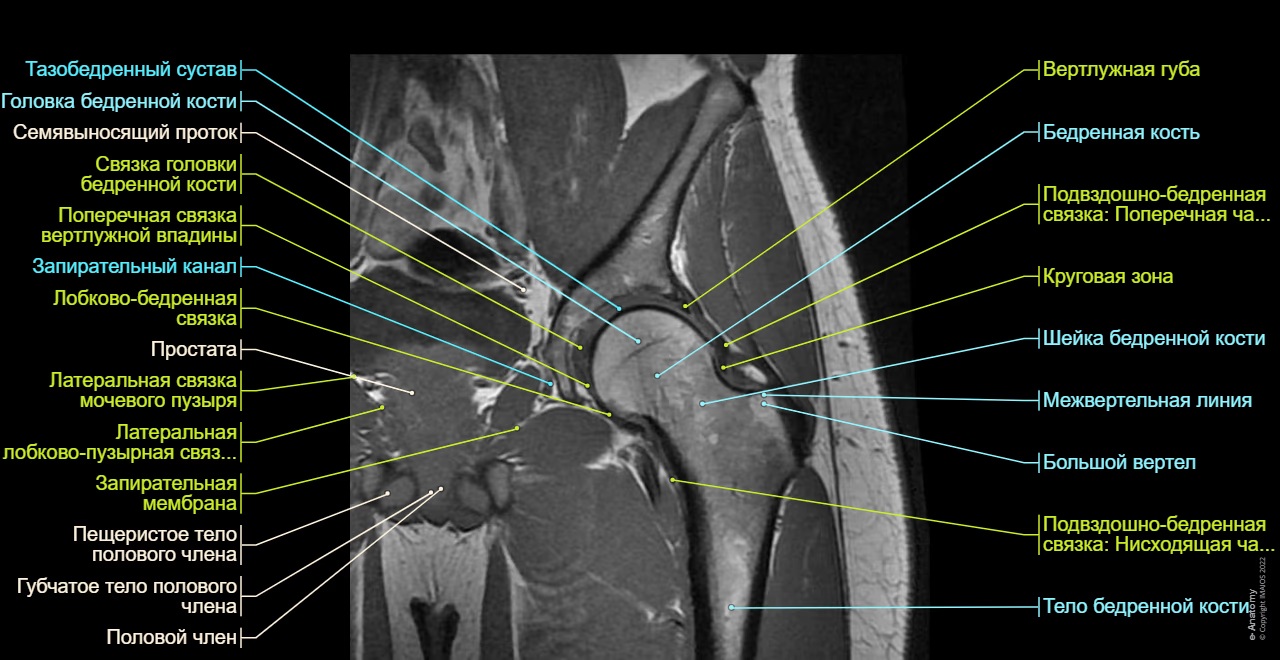

Анатомия тазобедренного сустава и что показывает МРТ

Тазобедренный сустав представляет собой шаровидное соединение, образованное головкой бедренной кости и вертлужной впадиной тазовой кости. Внутри сустава находится слой хрящевой ткани, обеспечивающей плавное скольжение при движении, а также суставная капсула, связки, сухожилия и прилегающие мышцы. Помимо опорной функции, тазобедренный сустав играет ключевую роль в амортизации и распределении нагрузки при ходьбе, беге и других движениях нижней части тела.

МРТ позволяет детально оценить состояние хряща, целостность связочного аппарата, наличие воспалительных процессов в суставной капсуле, а также определить повреждения сухожилий и мышц. Особенно информативны снимки при подозрении на остеонекроз головки бедренной кости, дисплазию, новообразования, скопление жидкости, скрытые переломы и микротрещины, которые часто не определяются на рентгене. Также МРТ способна выявить участки фиброзных изменений, отёков костного мозга и изменения, характерные для ревматических заболеваний. Исследование незаменимо в случаях, когда необходимо оценить степень повреждения мягкотканевых структур и выявить причины хронической или рецидивирующей боли, не объяснимой другими способами диагностики.